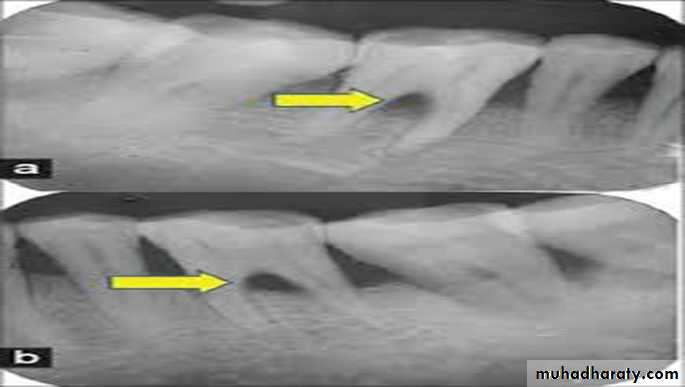

• Radiograph

PeriapicalBite-wings

Radiographs must always be obtained to confirm findings made during probing of a furcation-involved tooth.

the location of the interdental bone as well as the bone level within the root complex should be examined

it possible for furcation involvement to be present without detectable radiographic changes.

the localized but extensive attachment loss which may be detected within the root complex of a maxillary molar with the use of a probe will not always appear in the radiograph. This may be due to the superimposition in the radiograph of the palatal root of remaining bone

structure.